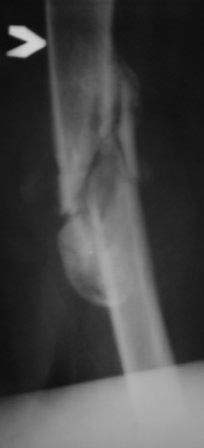

Уважаемые коллеги. Госпитализирован б-ной 47 лет, травма высотная 9 месяцев назад, тогда оперирован и/м остеосинтез (чрезвертельный перелом не диагностирован) в одном мед.объединение, через 3 месяца почему-то штифт удален. Больной ходит с двумя костылями, ногу не нагружает, выраженная патологическая подвижность в с/з бедра, в обл вертелов патологическую подвижность определить не удается, умеренная отечность всего бедра, укорочение около 4-5см. В плане в начале дистрактор, после устранения укорочение и репозиции БИОС реконструктивным стержнем( универсальным). Уважаемые коллеги помогите советом!, какие другие варианты, нюансы, случаи из практики! С уважением Абдурашид.

ЭОП унас нет, больной оперирован тогда, 35 дней назад, во время наркоза определена патологическая подвижность в вертельной обл, поэтому произведена остеотомия с исправлением угла, антеградный БИОС ,универсальный стержень ChM. Рентген снимки свежие фас и аксиальная. Пациент ходит с двумя костылями, ногу частично нагружает, лежа выпрямленную ногу поднимает.

На мой взгляд угол абсолютно не исправлен, а даже где-то уменьшился (106 гр. против 114), есть все условия для прорезывания шеечных винтов при нагрузке. Если открывали зону перелома, почему не выбрали в качестве импланта клинковую пластину?